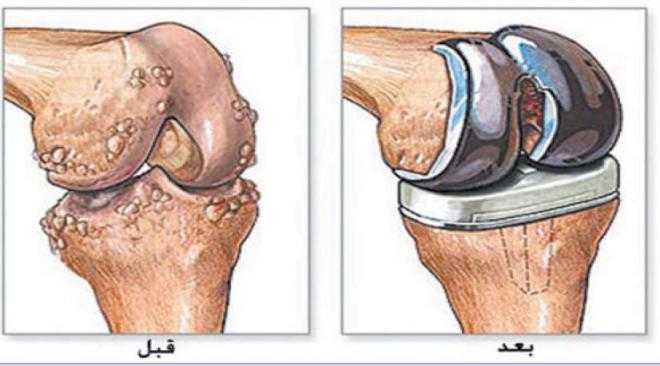

يعاني كثير من الأشخاص من مشكلة في المفاصل والتي تسبب الكثير من الألم بما يجعلهم في حاجة إلى القيام بعملية تركيب مفصل الفخذ الصناعي، وتعتبر جراحة تركيب مفصل امن الجراحات الشهيرة والناجحة الخاصة بعلاج مشاكل العظام، والتي يشعر بعدها المريض باختفاء الآلام وتحسن كبير في حركة المريض.

و تشتهر تلك الجراحة حيث يتم اللجوء إليها في حالات الإصابة خشونة مفصل الفخذ التي حدث بها تلف شديد بغضاريف المفصل، وتأتي الجراحة بعد تجربة العلاج الدوائي وإيجاد الطبيب أن تلك الطريقة لم تجدي نفعاً في علاج مشكلة المريض بالإضافة إلى شعوره بالألم الشديد الذي يصل لدرجة أنه يؤثر على أسلوب الحياة والحركة بصعوبة.

ما هي عملية تبديل مفصل الورك؟

وتتم العملية من خلال تركيب مفصل الفخذ وهو من الأطراف الصناعية، والذي يتكون من ثلاثة أجزاء وهي:

وتتم العملية من خلال استبدال الورك، حيث يقوم الطبيب الجراح بإزالة الأجزاء التالفة من مفصل الورك ويضع مكانها أجزاء تصنع عادةً من المعدن والسيراميك والبلاستيك شديد الصلابة، يساعد هذا المفصل الصناعي على تقليل الألم وتحسين الوظيفة.